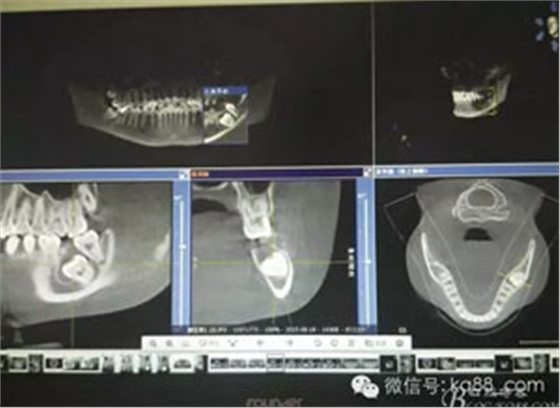

圖5.CBCT檢 查:下頜管位于38牙根的舌側(cè)。給手術(shù)提供避免損傷神經(jīng)的可靠保證。

5.jpg